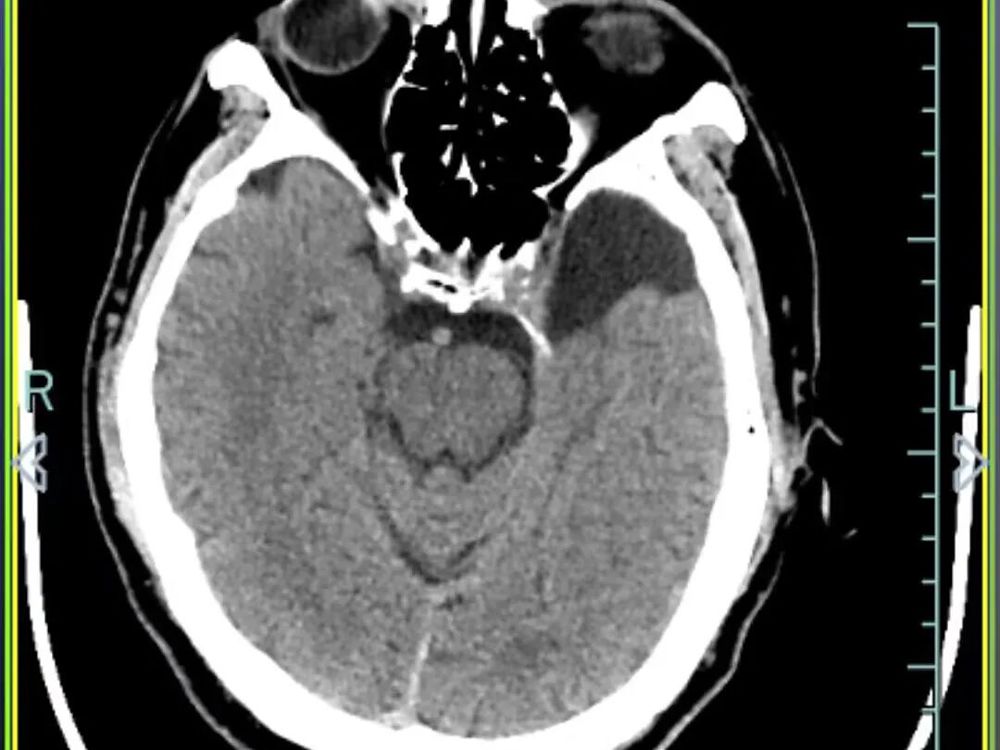

医院快速开通绿色通道并完善一系列检查后,诊断结果令人揪心:孙先生患有重型闭合性颅脑损伤,包括多发性创伤性脑出血、右侧颞部创伤性硬膜下出血、创伤性蛛网膜下腔出血以及脑震荡,同时合并多处骨折及软组织挫裂伤。

硬膜下出血、蛛网膜下腔出血和多发性创伤性脑出血

△10月4日CT复查显示,孙先生颅内出血全部吸收,骨折位置没有移位